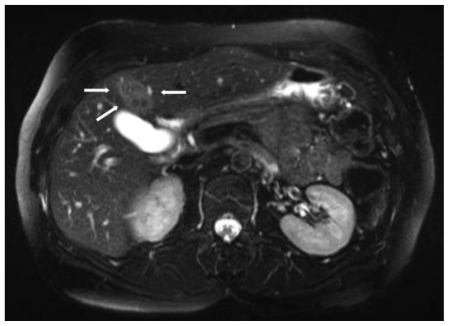

Axial T2-weighted fat-saturated image (30 minutes after injection of 1.4 mL ferucarbotran, TE = 96 msec, TR = 6684.4 msec, 6.0 mm slice thickness, 1.5 T Siemens MR scanner).

65-y-old woman with fasciola hepatica. The bulk of the lesion has become iso-intense to the rest of the liver (compare to Fig. 3a), leaving a cluster of small, sharply delineated individual nodules (arrows), clearly discernible from the rest of the liver parenchyma, with preservation of their bull's eye configuration.